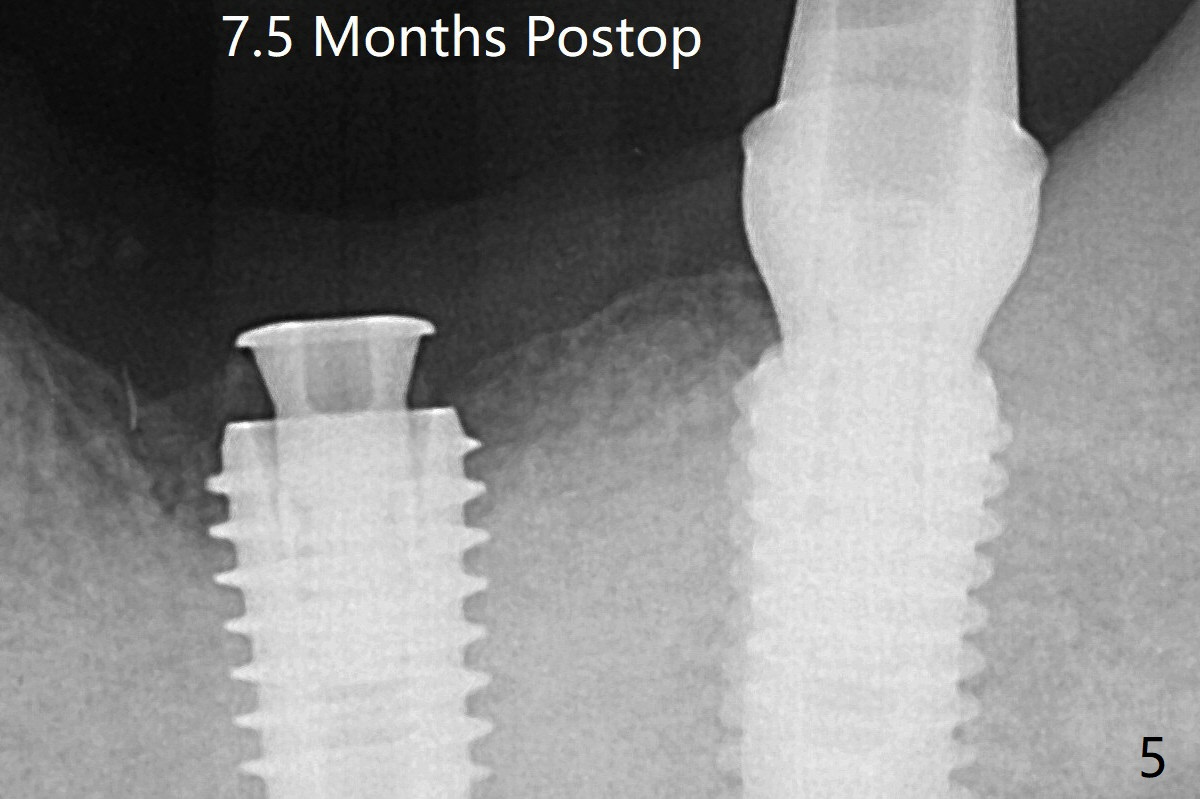

The mesial defect of #19 seems to have been repaired and the implant at #18 osteointegrates 7.5 months postop (Fig.5).